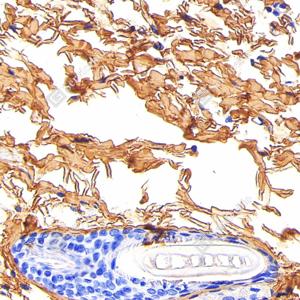

IHC检测Collagen I蛋白(货号 GB115707). 样品: 小鼠肺, 4%多聚甲醛 (货号G1101) 固定12-24小时. 抗原修复: 柠檬酸抗原修复液(干粉, pH 6.0) (G1201), 98℃, 20分钟. —抗: 1: 1000稀释, 4℃ 孵育过夜. 二抗: S-vision免疫组化多聚二抗(山羊抗兔),即用型 (货号G1302), 室温孵育20分钟. |